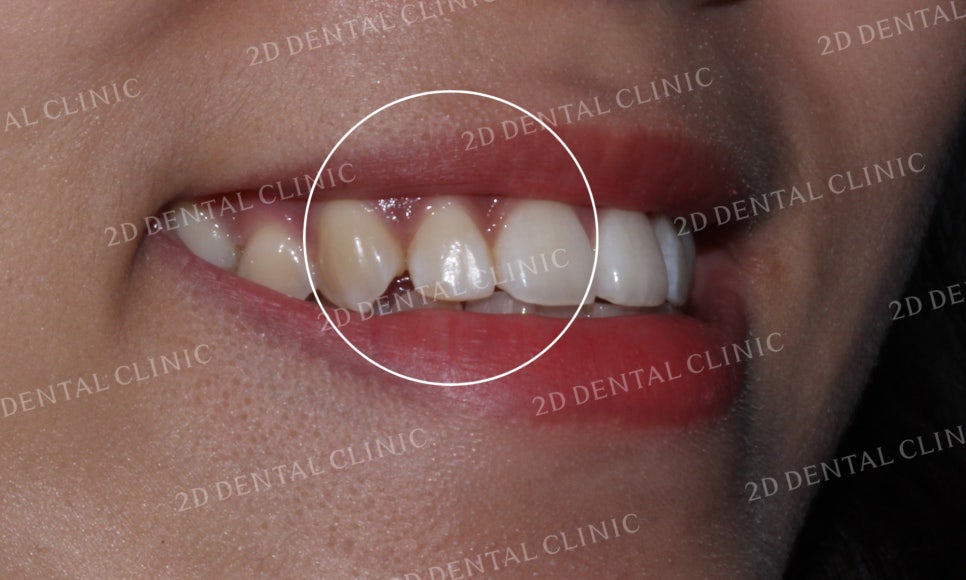

이번 환자분의 경우

토끼앞니와 함께

들쭉날쭉한 앞니를 가지신

Case에 해당하셨습니다.

입을 다물고 있는 상태의 사진입니다.

상악의 크라우딩과 함께

미세한 돌출이 발견된 상황이라

입을 다물었음에도 치아가

튀어나와 있다는 느낌이 강하게 나타납니다.